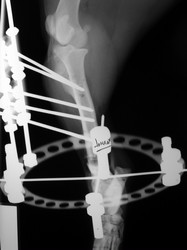

Fijación Externa

PRÁCTICAS CURSO DE FIJACIÓN EXTERNA PERFECCIONAMIENTO.

Híbrido.